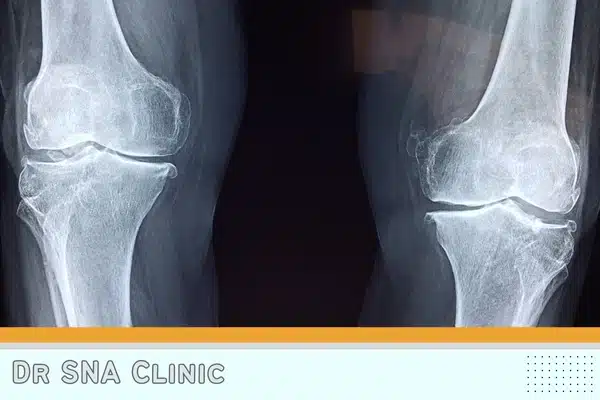

Knee osteoarthritis is an increasing health concern in the adult population. Nonsurgical treatment options for pain reduction and function improvement are limited in number…

Prior studies describing the treatment of symptomatic knee osteoarthritis with injections of bone marrow concentrate have provided encouraging results. The relationship between…